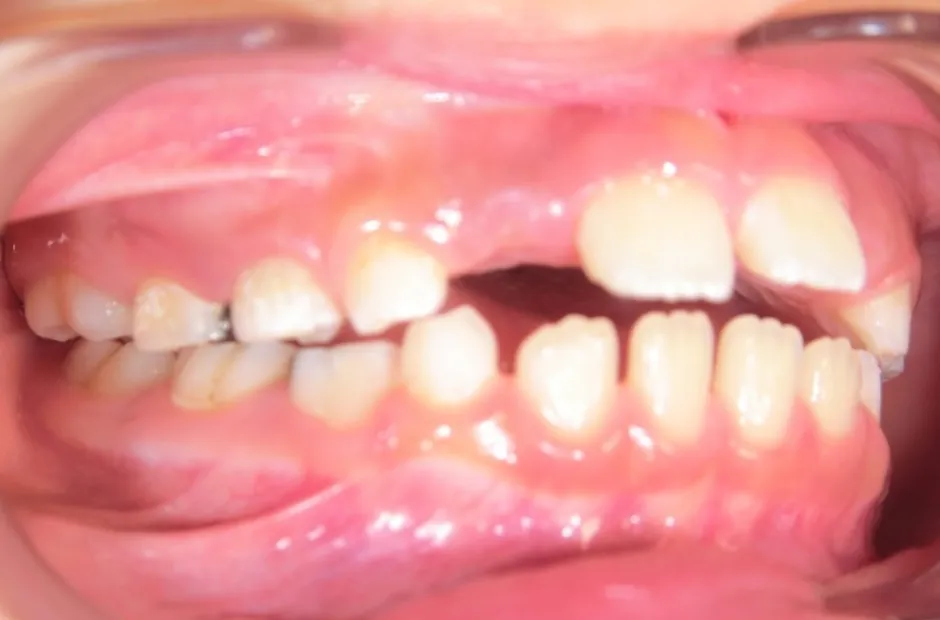

舌側弧線装置(タングクリブ付)

開咬、すきっ歯

| 診断名・主訴 | 開咬、すきっ歯 |

|---|---|

| 年齢・性別 | 7歳・男性 |

| 治療期間・回数 | 3年 |

| 治療に用いた主な装置 | 舌側弧線装置(タングクリブ付) |

| 抜歯部位 | なし |

| 治療費 | 30万円(税抜) |

| リスク・副作用 | 装置による違和感・疼痛・歯肉退縮・歯根吸収・虫歯のリスクなど |

治療前

治療後